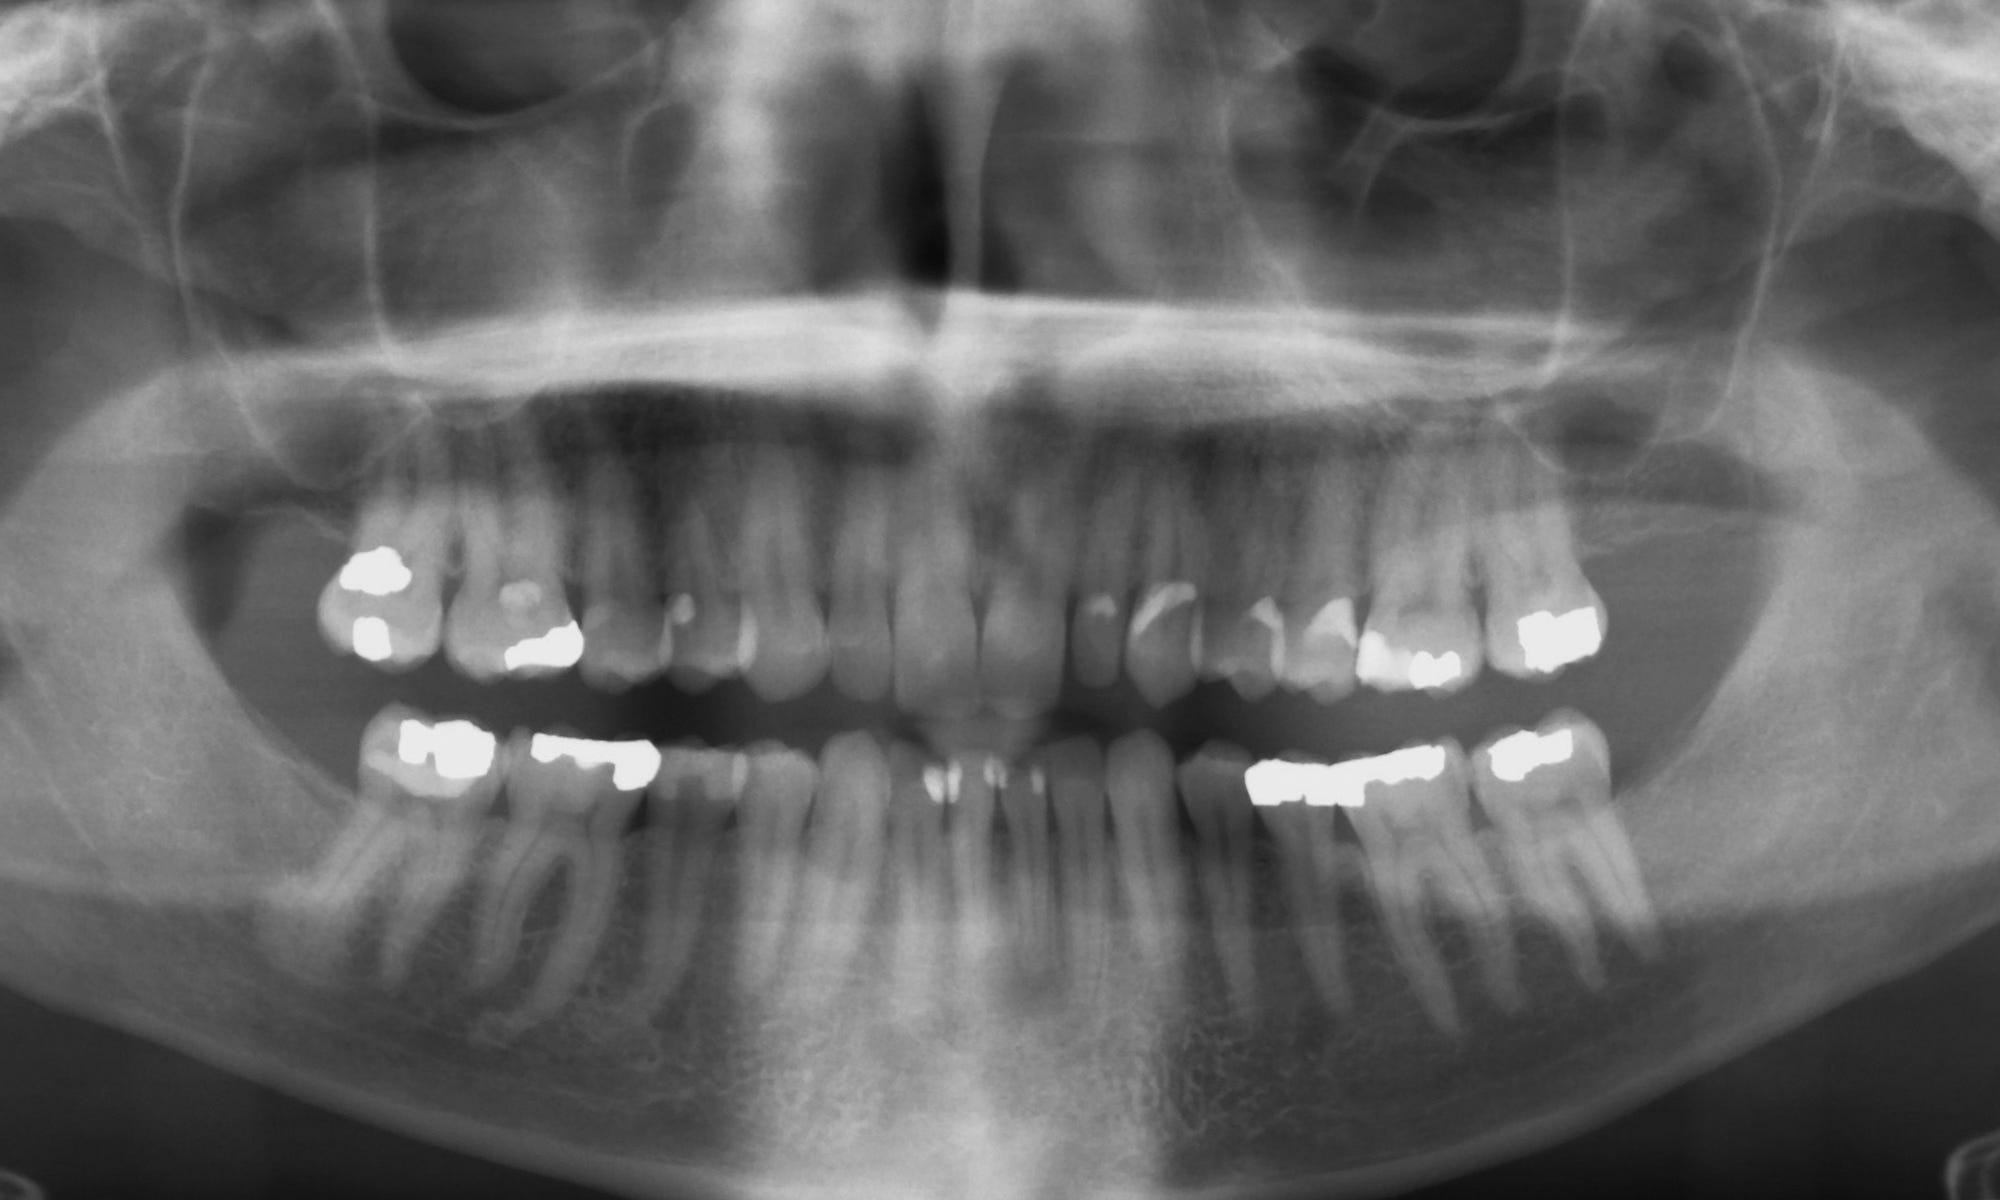

This was bad. Not bad because I missed those obnoxious cleanings where they look at my teeth, tell me it doesn’t look like I’m doing a good job flossing, and then brush my teeth with pumice and dirt, but because something very bad was going in my lower jaw. This time, my routine X-rays showed that I had “a significant amount of bone loss.”

“Wow, you have a significant amount of bone loss in your lower jaw.” They said.

The man told me that I had an abscessed tooth with an infection that went down so deep into my jaw that it was spreading to my other teeth. I was missing a lot of bone in my lower jaw and would probably need at least three root canals, and maybe even four.

In fact, he said, my jaw looked so bad that he recommended I have all four of my bottom teeth pulled and replaced with implants and bone grafts.

We waited for six months; then I scheduled a follow-up appointment with the periodontist. He said it appeared that, in fact, my three remaining teeth were still alive. And that, somehow, the bone had started growing back, which he had not been expecting. And that maybe we only needed to do the one root canal and that’s it. We may be able to save almost everything after all.

So I did, and he told me my three other teeth were still looking good; it appeared the infection had been completely stopped, and my lower jawbone had grown back even more.